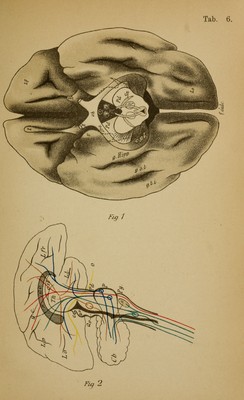

An atlas of the normal and pathological nervous systems : together with a sketch of the anatomy, pathology, and therapy of the same / Tr. and ed. (authorized) by Joseph Collins.

Credit: An atlas of the normal and pathological nervous systems : together with a sketch of the anatomy, pathology, and therapy of the same / Tr. and ed. (authorized) by Joseph Collins. Source: Wellcome Collection.